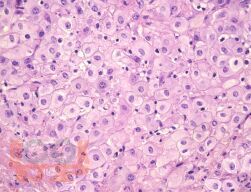

Монография посвящена анализу влияния урогенитальной инфекции на морфологию и функционирование плаценты у женщин с бессимптомным течением микоплазменной, уреаплазменной и хламидийной инфекций. Представлены современные данные о гистологическом строении компонентов маточно-плацентарной области – эндометрия, базальной децидуальной оболочки, ворсинчатого хориона. Освещена проблема формирования плацентарной недостаточности на фоне урогенитального инфицирования. Изложены результаты морфологического исследования плацент при разных видах урогенитального инфицирования.